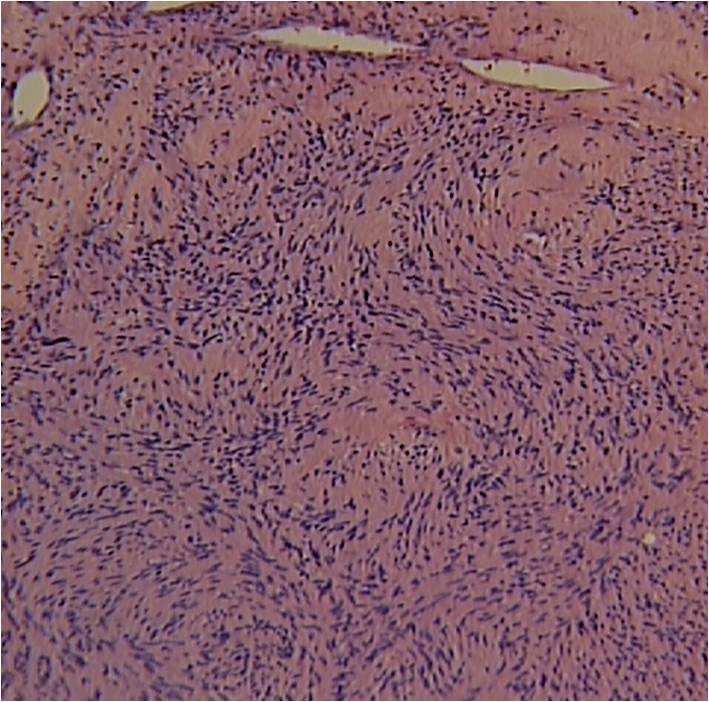

• Distinct Pattern of alternating Antoni A and B areas

o Antoni A Area: Cellular area arranged in short bundles or interlacing fascicles

Spindle cells with wavy appearing nuclei. (Fig. 5 & 6)

o Antoni B Area: Less cellular and more myxoid (Fig. 7)

Fig. 5-7 Microscopic Pathology demonstrates 2 different patterns; Antoni A area with spindled hypercellular distribution with wavy appearing nuclei (Fig 5 & 6A) that palisades, known as Verocay Bodies (Fig 6B). Antoni B area is less cellular and more myxoid (Fig 7) than the Antoni A area. Mitotic activity is not visible.